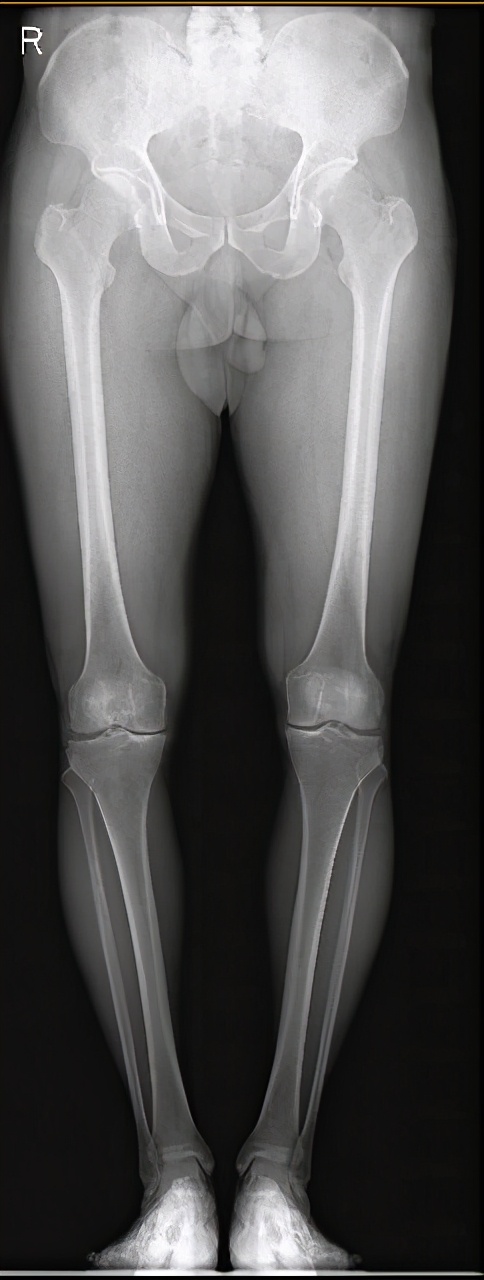

图7 膝骨关节炎全膝关节表面置换术a术前

图7 膝骨关节炎全膝关节表面置换术b术后

图7 :a图示双膝骨关节炎严重、外翻畸形。b图示右侧全膝关节表面置换术后